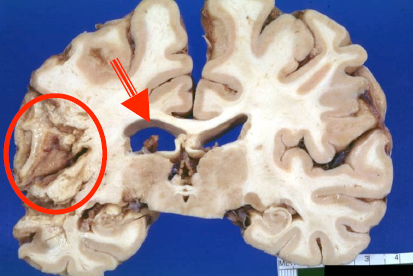

What is caused the area in the circle? What is the finding the arrow is pointing to?

Cystic cavity surrounded by gliotic tissue with glial strands (circle)

– There is compensatory (ex-vacuo) ventricular enlargement